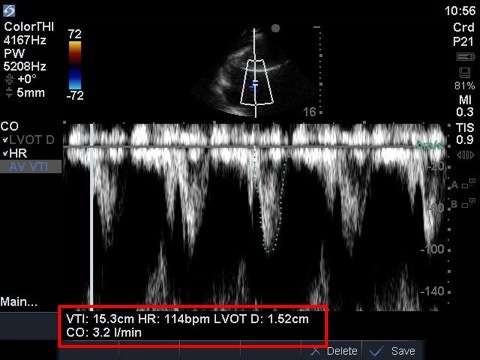

Cardiac 2 Stroke Volume Machine Calculations Image